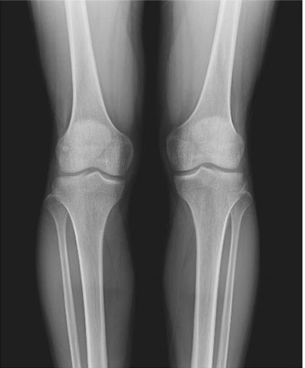

臨床圖片

微信圖片_20210927001109